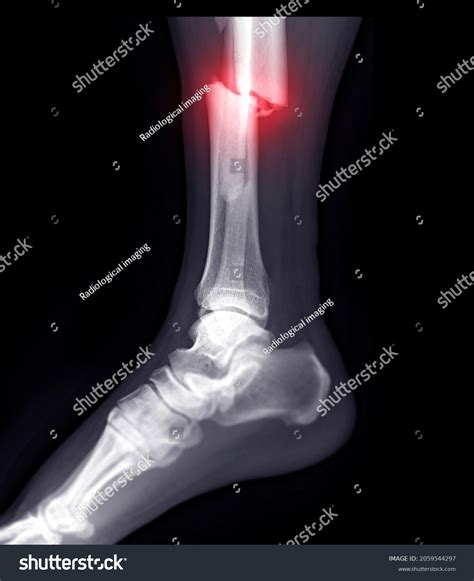

Experiencing a sudden, sharp pain in your ankle after a fall or an awkward twist can be a frightening experience. One of the most critical steps in diagnosing the severity of this injury is obtaining a broken ankle Xray. This medical imaging test is the gold standard for determining whether the bone is fractured, the extent of the damage, and the appropriate course of treatment. Whether you are dealing with a simple hairline fracture or a more complex break involving multiple bones, understanding what to expect during the imaging process and how to interpret the results is essential for your recovery journey.

When you visit an urgent care clinic or an emergency room with ankle pain, the physician will first perform a physical examination. However, even the most experienced doctor cannot confirm a fracture just by looking at the surface. A broken ankle Xray is necessary to visualize the internal structure of the joint. It provides a clear, two-dimensional image of the tibia, fibula, and talus, allowing medical professionals to rule out or confirm a break.

By securing an image, the radiologist or orthopedist can identify the exact location and pattern of the break. This accuracy is vital because different types of fractures require vastly different treatments, ranging from simple immobilization in a walking boot to surgical intervention with plates and screws.

Once the images are captured, they are reviewed by a radiologist. The broken ankle Xray will reveal whether there is a cortical breach—the medical term for a break in the bone's outer shell. The report will describe the type of fracture, which helps the orthopedic surgeon plan the treatment.